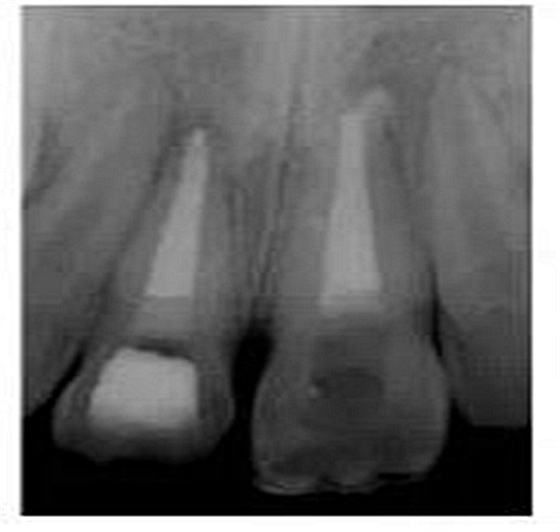

切端則采用透明樹(shù)脂,最后使用釉質(zhì)樹(shù)脂(Amaris, VOCO, Cuxhaven, Germany)。21的樹(shù)脂修復(fù)采用類似的方式。修復(fù)初步成型,拋光,恢復(fù)干燥牙釉質(zhì)的顏色。攝片顯示樁在根管內(nèi)位置合適(圖15)。最后一次復(fù)診精修、拋光充填體,完成治療。